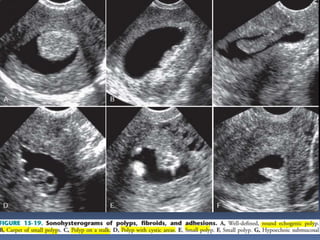

This document contains an image gallery from Dr. Mohit Goel showing various uterine anomalies and ovarian cysts. It includes images of an arcuate and unicornuate uterus, endometritis, a twisted ovarian pedicle, dermoid cysts of varying sizes and echogenicity containing hair, fat, and calcifications, and a combination dermoid cyst showing both mesh and plug structures. The gallery provides ultrasound images of different gynecological conditions for medical education and reference.